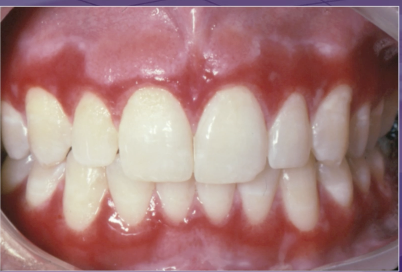

what is NOT part of the differential dx

lichen planus

pemphigus vulgaris

erythema multiforme

mucous membrane pemphigoid